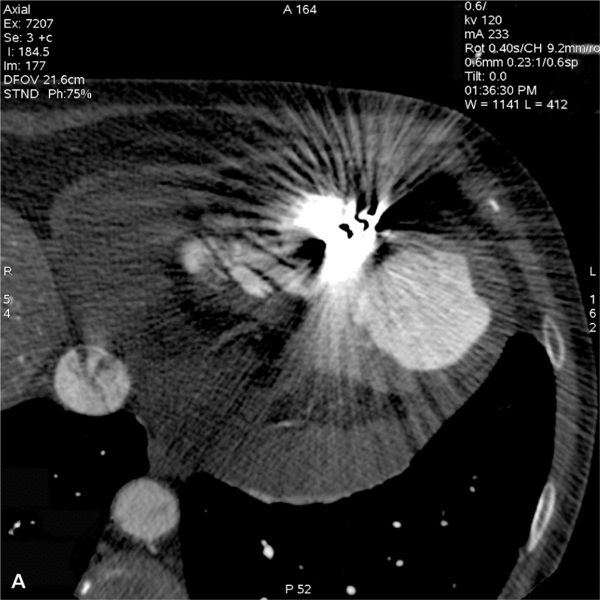

• przemieszczenie końcowego odcinka elektrody poza światło prawej komory uwidocznione dopiero po ponownej prośbie kardiologa, aby zwrócić uwagę na położenie końcówki elektrody, co wymagało zmiany szerokości i długości okna rekonstruowanego (często nie udaje się postawić rozpoznania z powodu masywnych artefaktów od elektrody) (ryc. 1A, B),

RYCINA 1. Badanie serca metodą TK. [A] Warstwa poprzeczna na standardowym oknie. Masywne artefakty od elektrody całkowicie uniemożliwiają ocenę jej położenia względem ściany prawej komory. [B] Warstwa rekonstrukcji MPR w linii elektrody po odpowiednim ustawieniu okna. Dystalny odcinek elektrody nieznacznie przemieszczony o 5 mm poza światło prawej komory.